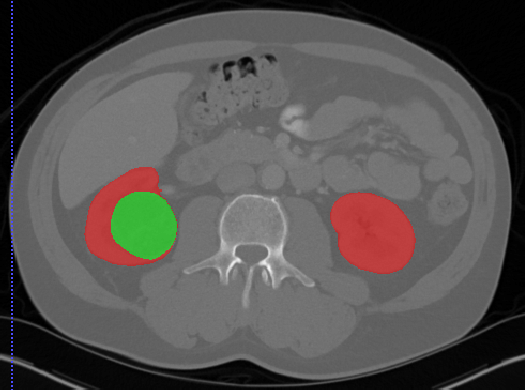

肾脏

Kits19

| 名称 | 标注内容 | 类型 | 模态 | 数量 | 标签格式 | 文件格式 |

|---|---|---|---|---|---|---|

| Kits19 | 肾肿瘤 | 分割 |